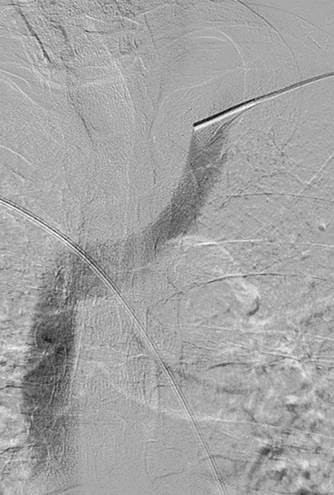

Trombectomía de injerto de vena axilar-arteria braquial izquierda.

Injerto AV con trombosis y con estenosis en anastomosis venosas.

Catéteres DVX de AngioJet en injerto AV.

Imagen tras la activación del sistema AngioJet en el lado venoso del injerto AV.

Imagen tras la activación del sistema AngioJet en el lado arterial del injerto AV.

Dr. R. Jones, radiólogo intervencionista, Queen Elizabeth Hospital Birmingham (Reino Unido)